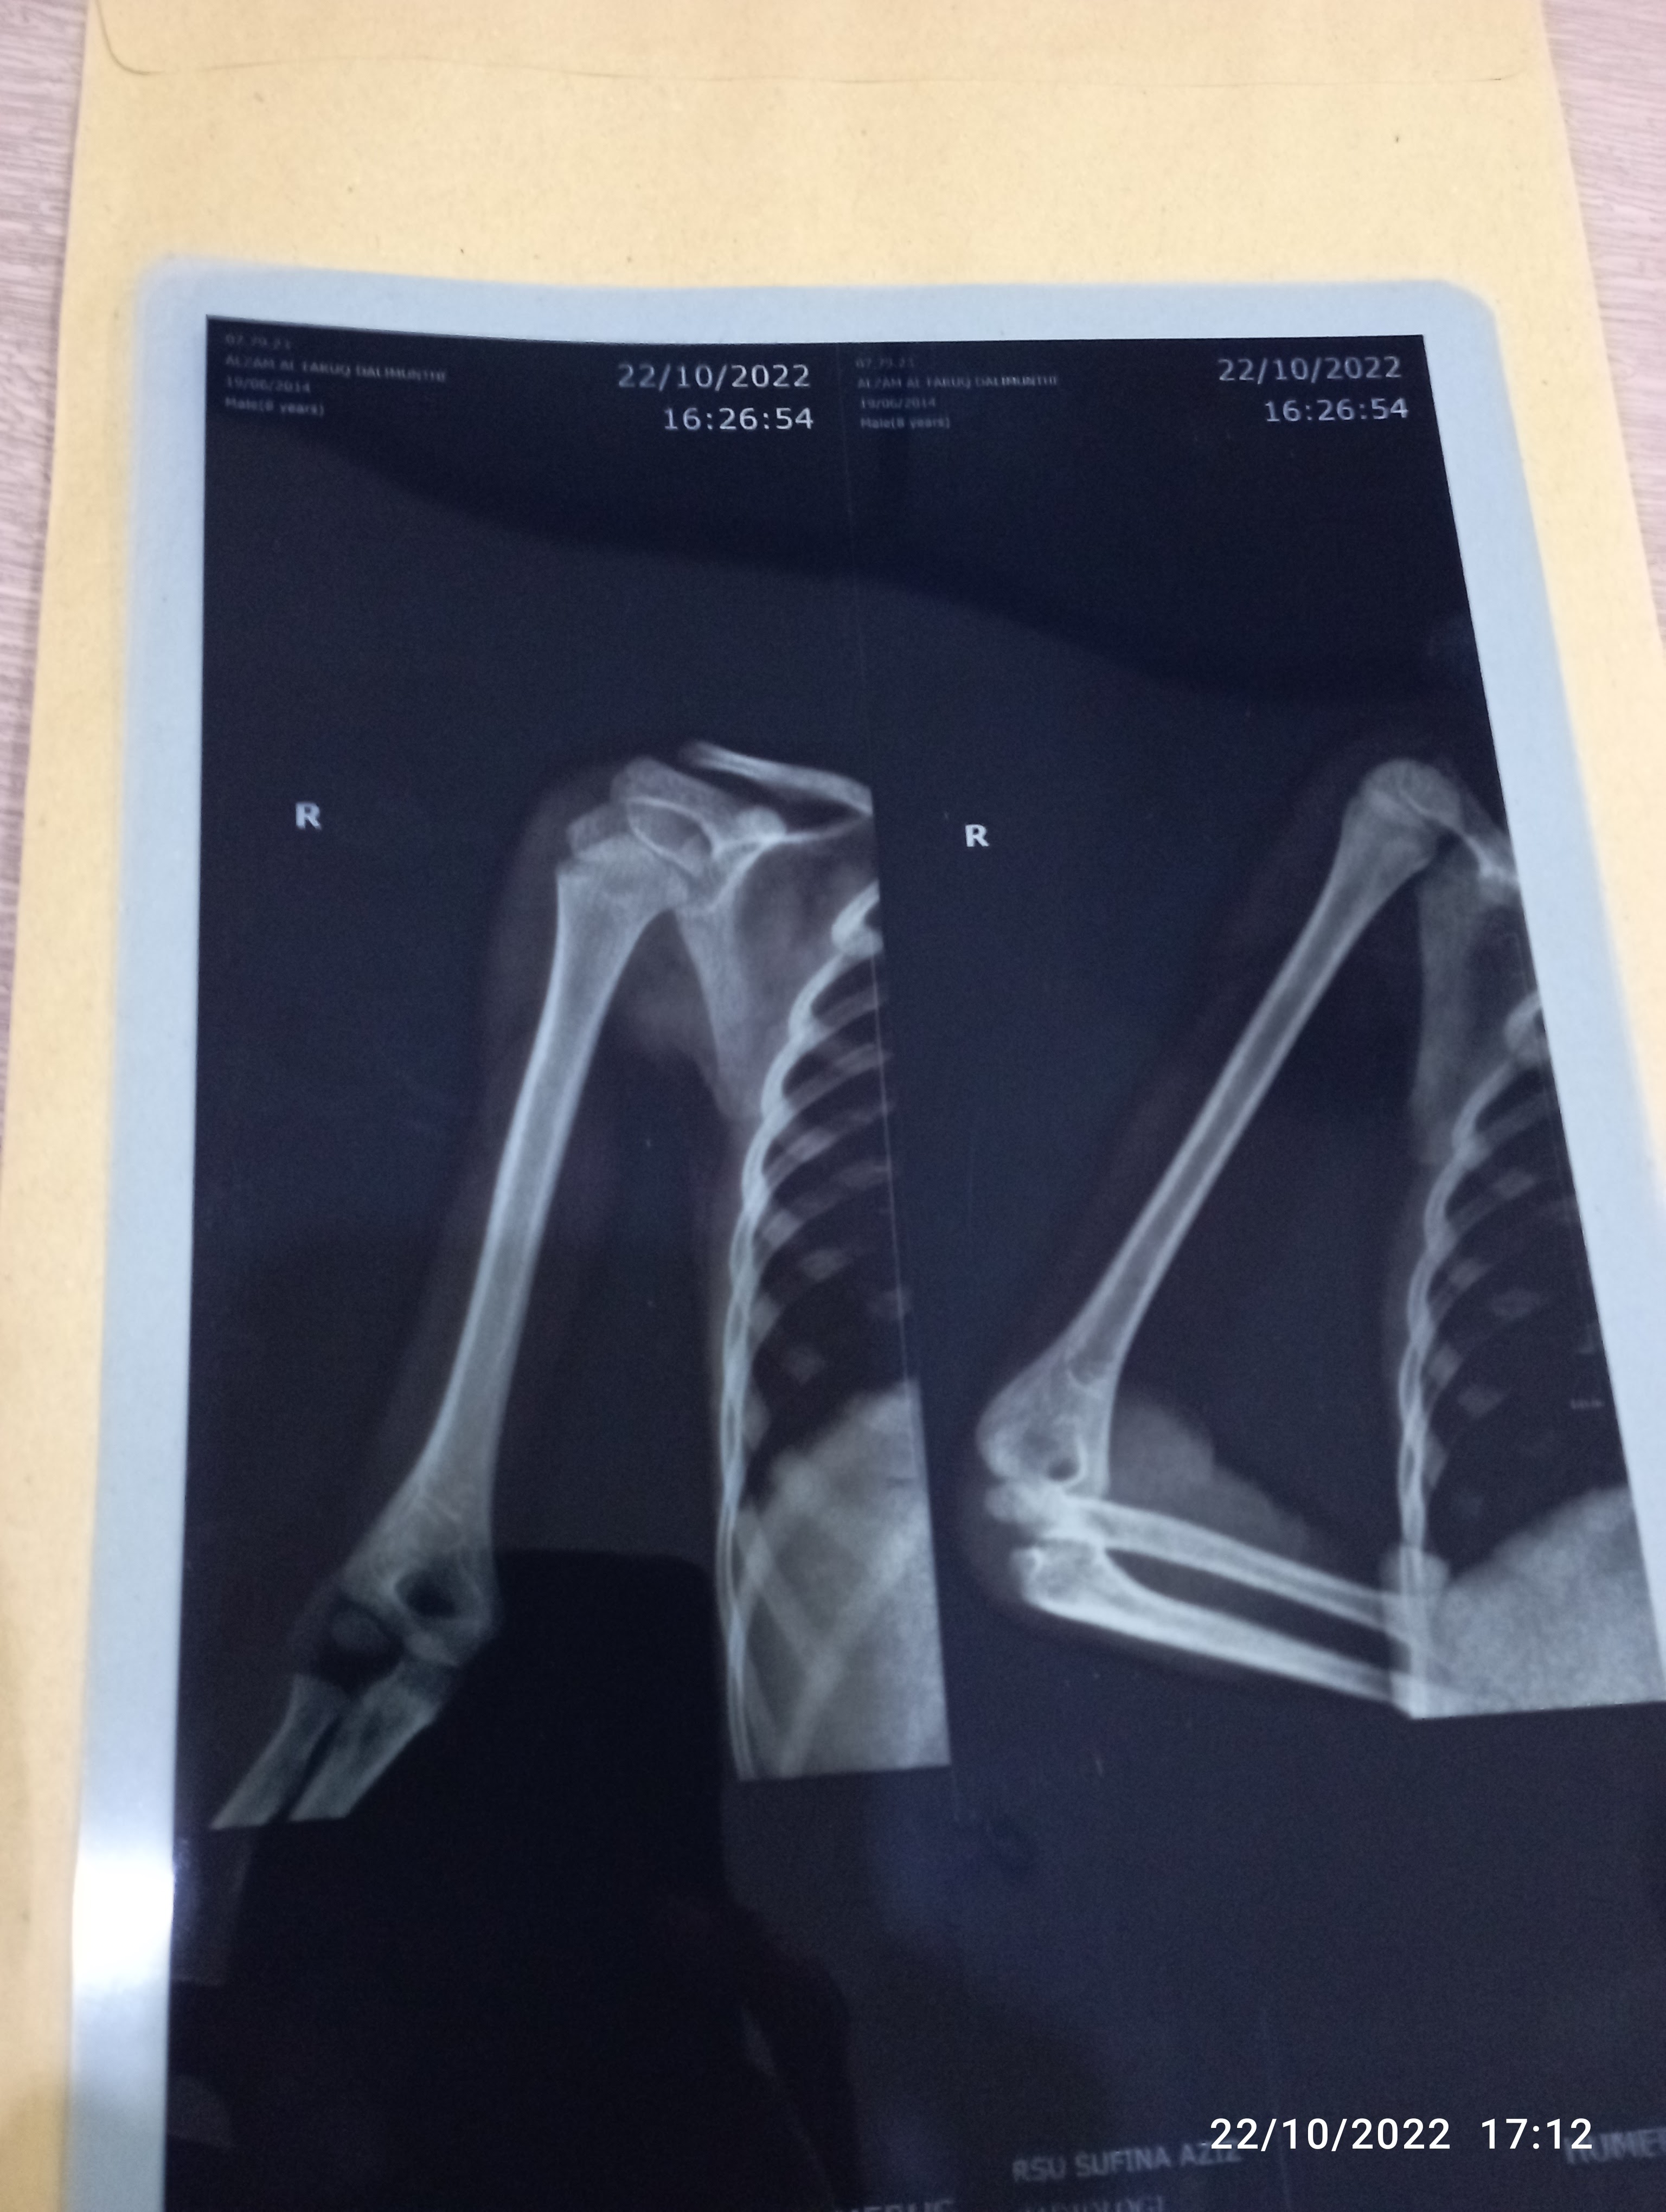

Menunggu sampai sore baru ketemu dokter anak, kemudian tangannya dirontgen agar terlihat jelas apakah hanya dislokasi atau ada fraktur (retakan). Hasilnya baru bisa dibacakan di hari Selasa (mengingat saat itu adalah hari Sabtu). Sebenarnya pun aturan BPJS bertemu dokter sepekan sekali. Namun dokter memberi keringanan agar si anak cepat dapat penanganan. Alhamdulillah.. Terimakasih dok!

Selasa bertemu dokter hasilnya baik-baik saja. Tidak ad fraktur, hanya dislokasi ringan. Namun si anak tidak bisa melakukan beberapa gerakan seperti meletakkan tangan di dada atau memegang bahu. Dokter anak merujuk kembali ke dokter spesialis tulang atau ortopedi. Namun di rumah sakit berbeda karena rumah sakit Sufina Azis tidak memiliki ortopedi.

Hampir jam 12 dokter spesialis datang. Hanya 5 menit melihat hasil rontgen dari RS rujukan dan berkomentar " Gak ada masalah kok anaknya.. Dikompres saja bisa sembuh". Emak langsung gahar donk. "Gak ada masalah gimana Dok, si anak gak bisa pegang dada dan bahu. Itu artinya ada masalah.. " Dokter pun akhirnya memberi rujukan ke fisioterapi.